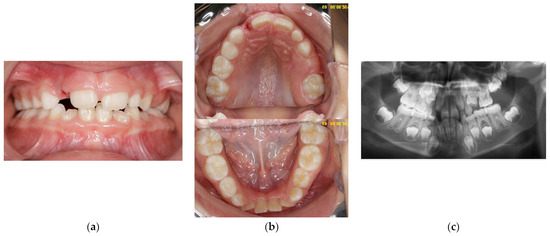

At the age of 7 y and 10 m, 65 had erupted, with an atypical crown shape and size (larger than usual, almost like a first permanent molar) (Figure 3a,b). Furthermore, no premolar buds could be seen in the upper left quadrant, and the unerupted 26 had reached the coronal stage, while 27 had a delayed development as compared to 17 (Figure 3c). Tooth 64 had become more intruded and seemed to be impacted by 63. PFE of the upper left permanent molars was suspected. Bimaxillary crowding and class II malocclusion were also noted. Caries prevention measures were applied, such as professional cleaning and glass-ionomer sealants on erupted first permanent molars (16, 36, and 46).

Figure 3.

Age of 7 y and 10 m. (a) Frontal view showing slight shift of the upper midline to the left and lower crowding; (b) occlusal view of both arches: 65 fully erupted, with atypical crown shape and size; (c) panoramic X-ray showing impacted 64, bimaxillary crowding, and a tendency for re-inclusion of 74.